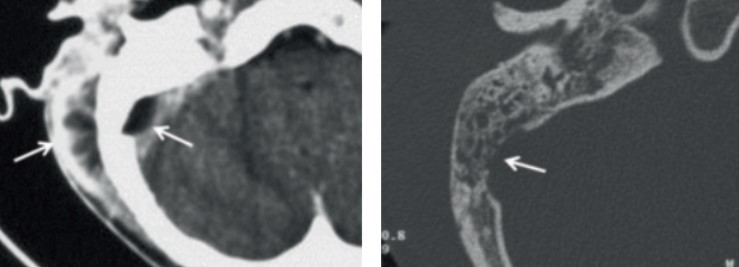

Question 1 : Quelles affirmations sont exactes en ce qui concerne l’otoscopie suivante (figure 1) ?

Le tympan ici est couleur chamois. Ceci est spécifique d’une rétention séreuse rétro-tympanique. On voit de plus une bulle liquidienne dans le quadrant postéro-inférieur.

Le quadrant antéro-inférieur est l’endroit privilégié pour réaliser les paracentèses ; il est reconnaissable (attention ! sauf dans les otites moyennes aiguës) par le triangle lumineux qui le délimite. Pour repérer le côté de l’otoscopie il faut garder en tête que le manche du marteau et son col forment un angle ou une flèche qui pointe vers l’avant du patient. Ici on est donc bien à gauche.